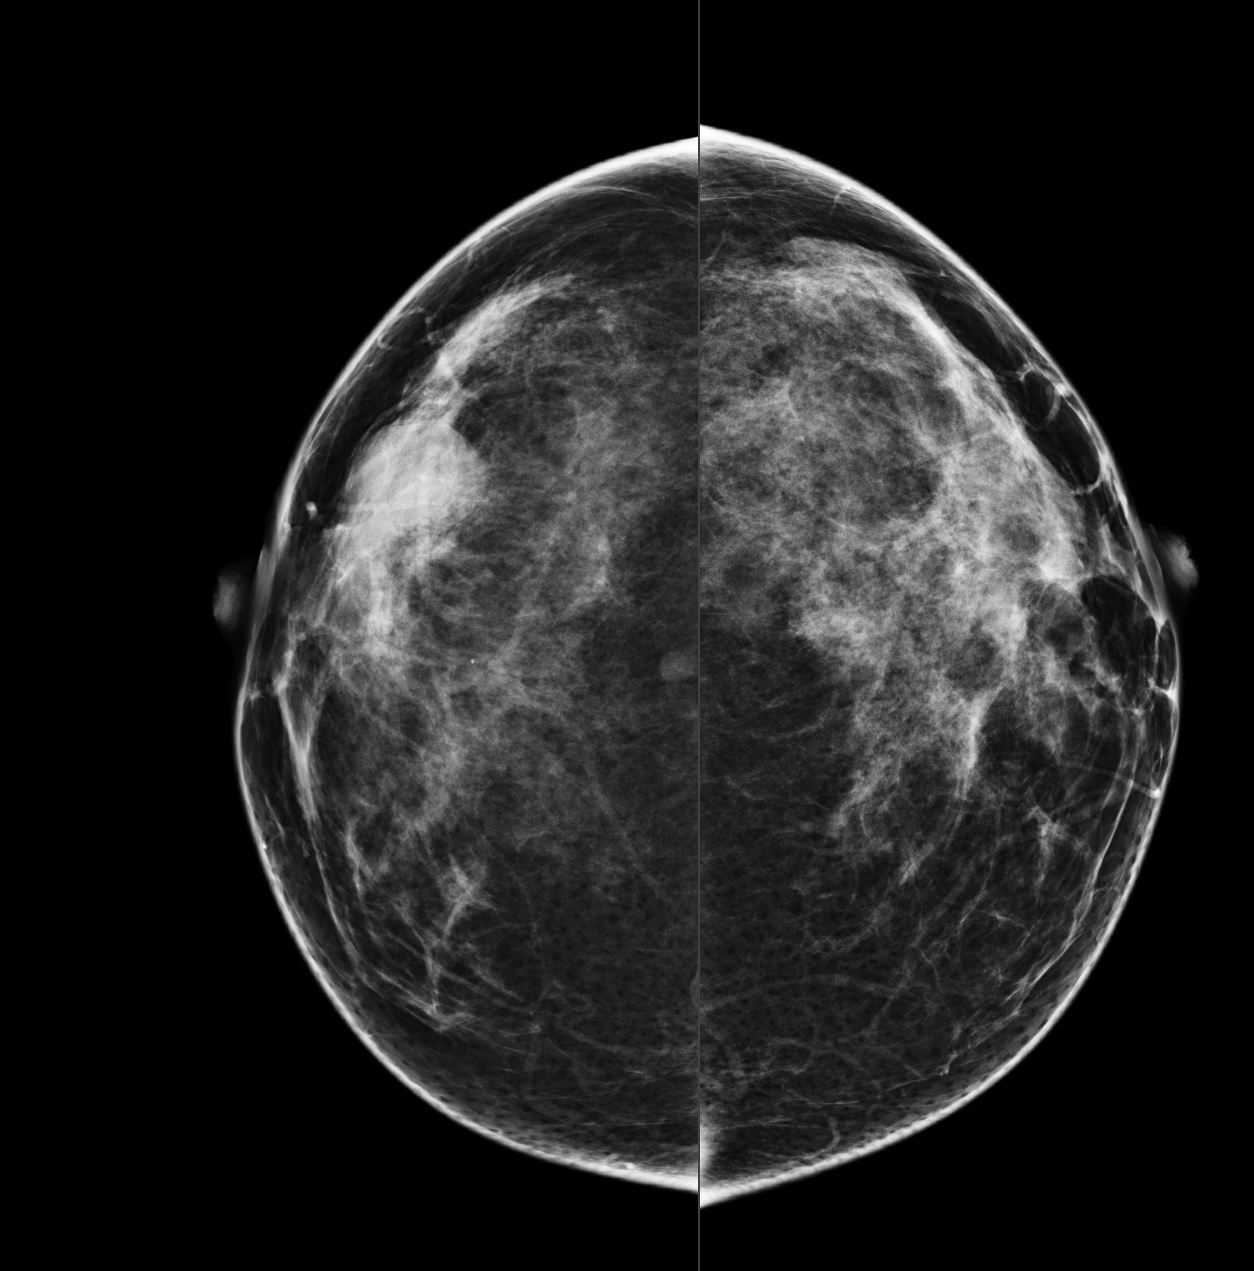

Bilateral Digital mammography , Craniocaudal (CC) and Mediolateral oblique (MLO) view with tomosynthesis images revealed a round shaped, equal density mass with indistinct margin in lower outer quadrant. No suspicious microcalcifications was seen. No significant axillary lymph nodes were present. A high resolution ultrasound of the right breast showed a round shaped, heterogeneously hypoechoic mass with irregular margin, small cystic spaces within and posterior acoustic enhancement, measuring about 1.6x1.9x1.5cm at 7 O’clock position. Mild internal vascularity was noted on colour doppler images. Right axilla showed suspicious lymph nodes with loss of fatty hilum and thickened cortex.

Although the mass has few benign features like round shape and posterior enhancement, presence of irregular margin and axillary nodes with thickened cortex and loss of fatty hilum points towards the suspicious nature of the mass. So, the mass was classified as BIRADS category 4b lesion. Ultrasound guided biopsy of the mass was suggestive of invasive breast carcinoma with possibility of medullary carcinoma. IHC study showed tumor to be Positive for PR and negative for ER and HER2neu receptors. Patient underwent Breast conserving surgery with right axillary lymph node dissection and final histopathological report was Invasive carcinoma with medullary features. Axillary lymph nodes were involved by the tumor.